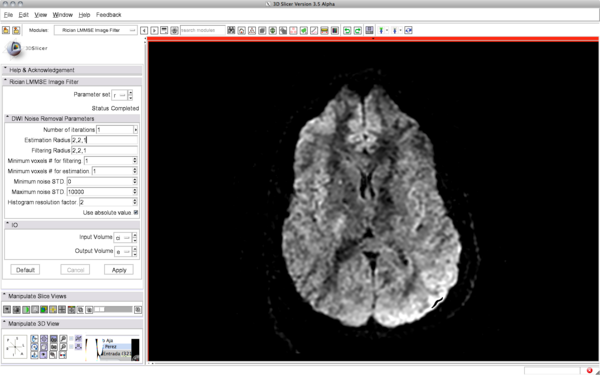

After filtering: